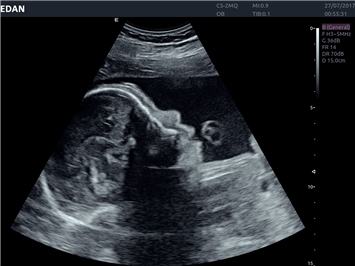

Объемное сканирование:

Да

4D:

EDAN Acclarix AX8 представляет собой компактную высокотехнологичную ультразвуковую систему, сочетающую передовые технологии визуализации с интуитивно понятным управлением и улучшенной мобильностью.